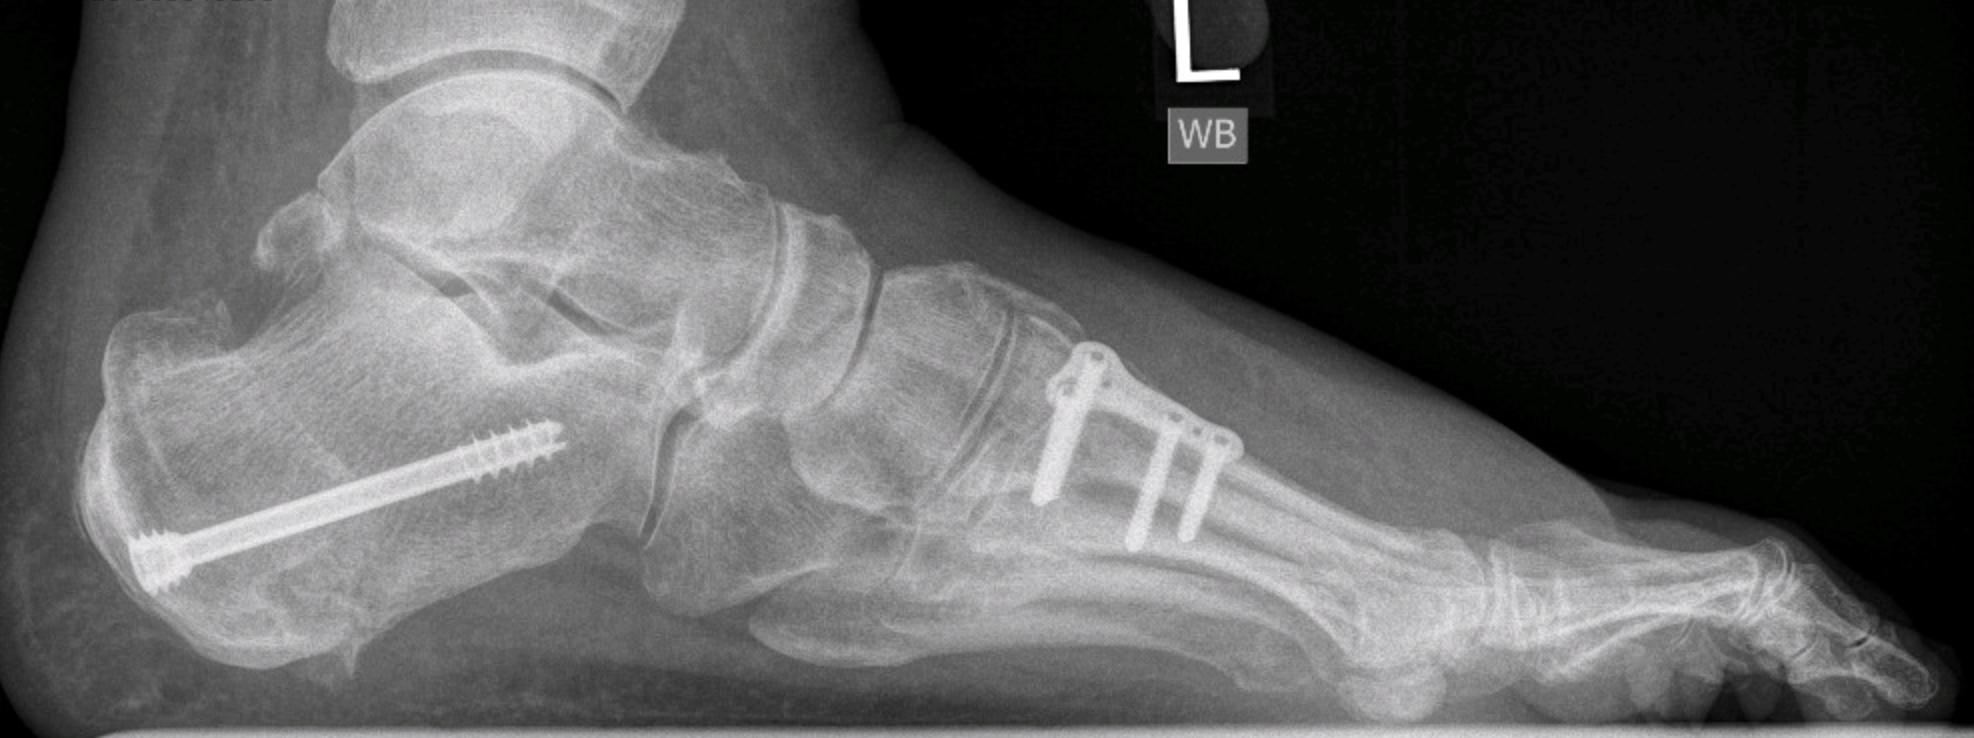

FIgure 4: Radiograph of a cavovarus foot treated with calcaneal osteotomy, extension osteotomy of the first ray and tibialis posterior tendon transfer. Note - despite excellent correction, the patient required subsequent exostectomy of calcaneal plantar prominence.